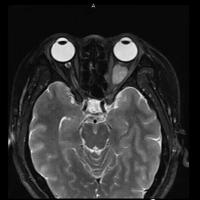

女,54岁,头痛头晕月余,无眼部症状及视力异常。 影像表现:右侧眼球后方占位病变,考虑海绵状血管瘤可能性大,鉴别:视神经鞘瘤、脑膜瘤及炎性假瘤。 病例点评:眼眶内血管瘤是较常见的良性肿瘤,其中以海绵状血管瘤最常见。可发生于任何年龄,主要表现为眼球突出及偏位,在低头或哭泣时可有突眼加重。可经眶缘触及具有压缩性的肿块。视力损害多较缓慢。肿块大多位于肌锥内,其次为肌锥外,平扫呈边界清楚的圆形、卵圆形或分叶状肿块,增强扫描呈缓慢进行性显著强化为其特征性表现。